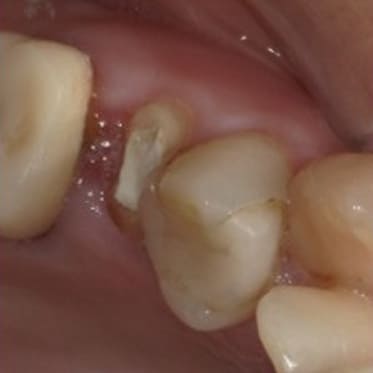

歯を抜かない治療(C4)

不幸にも、虫歯が進行して骨に埋まっている部分の歯(歯根)まで細菌感染が起こってしまった場合(C4)、通常では抜歯が適応治療になります。 しかし、歯根まで虫歯が進行してしまっている場合の多くは痛みが無いのも特徴です。 特に痛みも無いのになんで歯を抜かなければならないかとお思いの患者様も多くいらっしゃいます。 生物学的・医学的には抜歯が適応であったとしても、患者様のご希望と、精密検査の結果から、当院では歯を抜かずに温存する治療も行っております。 もう歯がほとんど残っていないから歯を抜かなければならないと諦めていらっしゃる患者様も、ぜひ一度当院にてご相談、検査をさせて下さい。